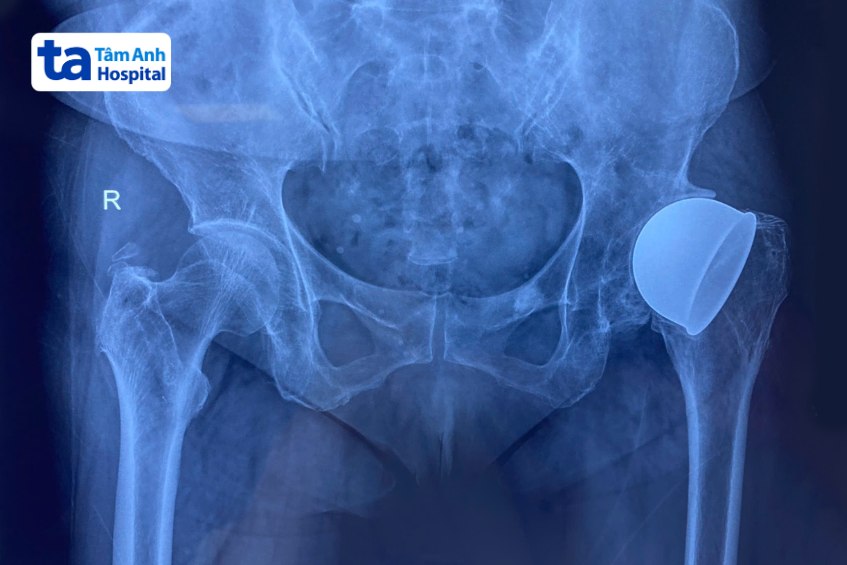

Kết quả chụp X-quang cho thấy chỏm xương đùi trái và khớp háng bên trái của bà Hà biến dạng hoàn toàn, còn sót lại các dụng cụ từ lần phẫu thuật trước. Người bệnh đau nhiều và chân trái ngày càng ngắn lại. Với khớp gối phải, kết quả X-quang cho thấy khớp đã bị thoái hóa giai đoạn cuối, cần phải phẫu thuật sớm nếu không mất khả năng vận động. Bà Hà còn bị vẹo trục chi, hai chân lệch nhau.

Bà Hà xuất viện, ổn định sức khỏe. Sau hơn 6 tháng, bà nhập viện lần hai để điều trị khớp háng bên trái. Bác sĩ tiếp tục chỉ định thay khớp háng nhân tạo bên trái cho bà Hà để giải quyết các triệu chứng và khôi phục khả năng vận động.

Đối với khớp háng nhân tạo, để tìm ra loại khớp phù hợp với người bệnh, bác sĩ đã sử dụng phần mềm TraumaCad phác thảo lại hình dạng khớp háng, tính toán độ sâu ổ cối, chiều dài chuôi khớp… Từ đó quyết định dùng khớp có gờ chống trật để đảm bảo độ vững cho khớp nhân tạo, giúp người bệnh vận động thoải mái và linh hoạt hơn.

Ngoài ra, xương của bà Hà rất mềm do bệnh nền loãng xương, vì vậy bác sĩ đã thay khớp háng nhân tạo chuôi dài thay vì chuôi ngắn như thông thường. Chuôi dài cắm sâu vào ống tủy xương đùi, giúp tăng diện tích tiếp xúc và cố định khớp; phân tán lực tốt hơn, giảm nguy cơ gãy thân xương đùi. Trong quá trình phẫu thuật, chiều dài hai chân của người bệnh cũng được điều chỉnh cân bằng trở lại.